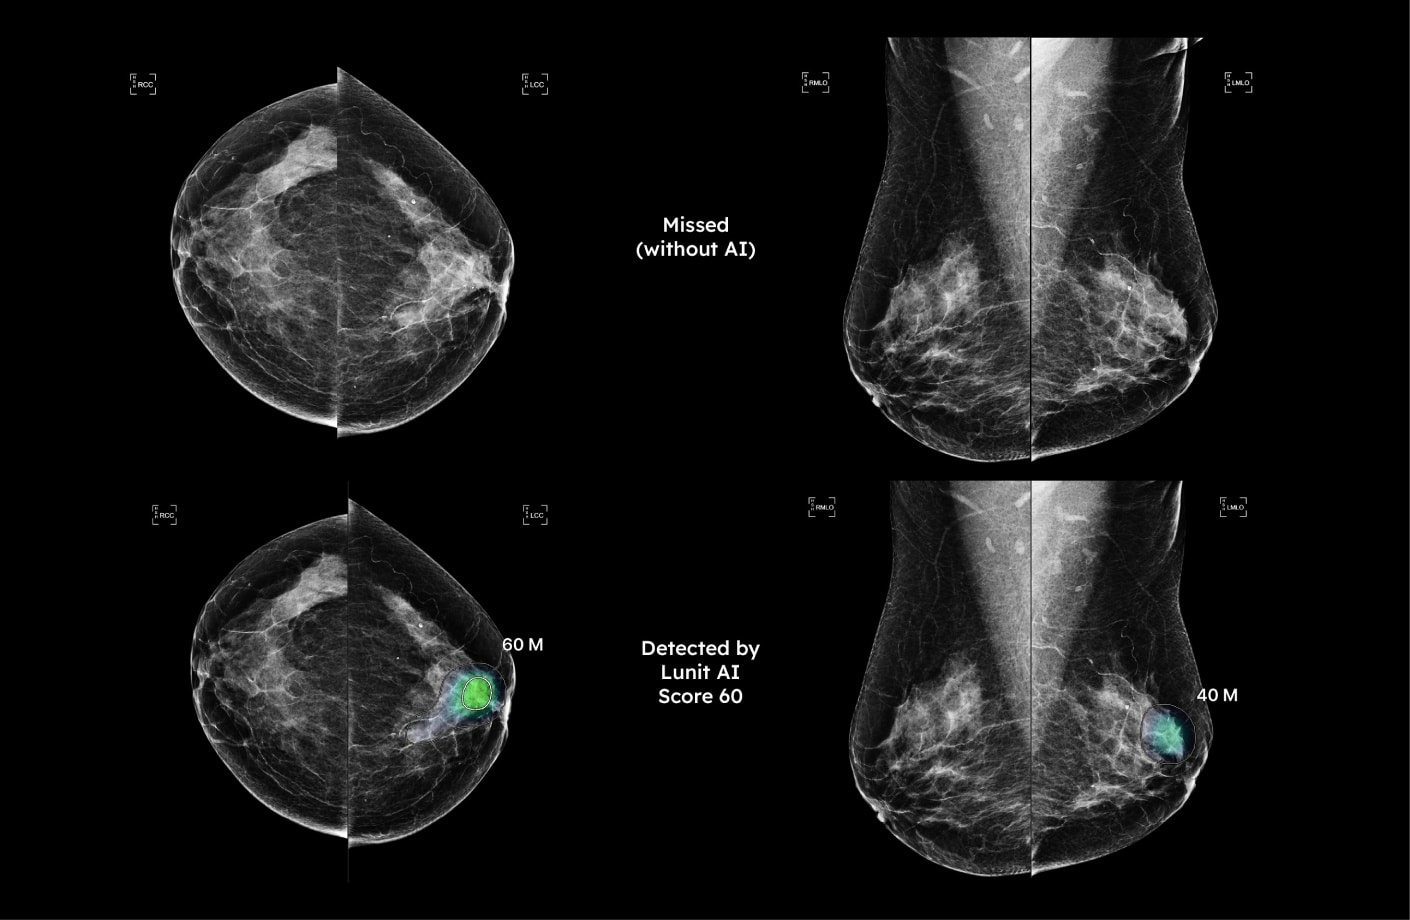

Backed by over 400+ peer-reviewed publications, our AI delivers world-class performance across multiple imaging modalities.

From mammograms to chest X-rays, Lunit’s technology enhances diagnostic confidence and consistency in the most diverse clinical environments.